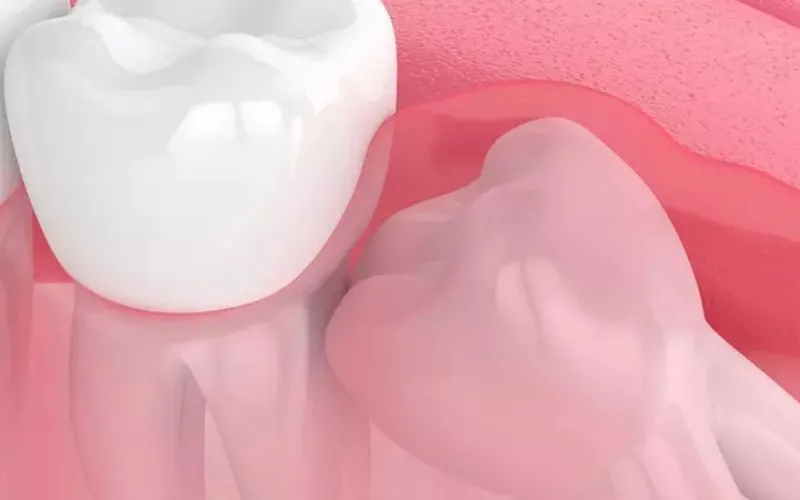

Viêm lợi trùm là một trong những bệnh răng miệng phổ biến nhiều người mắc hiện nay. Người mắc phải sẽ cảm thấy khó chịu và đau

Bệnh viêm lợi trùm là bệnh mà bất kì ai cũng có thể gặp phải, đặc biệt ở bà bầu. Bà bầu mắc phải sẽ cảm thấy